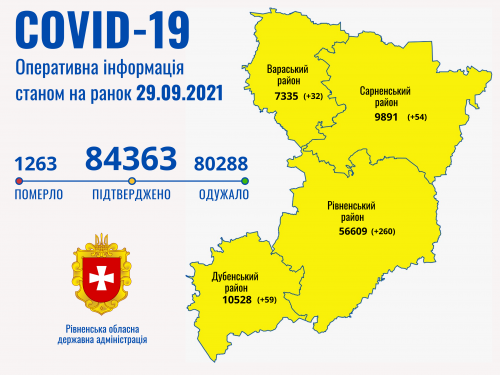

Пів тисячі - у важкому стані, 9 жителів Рівненщини померли за добу від коронавірусу